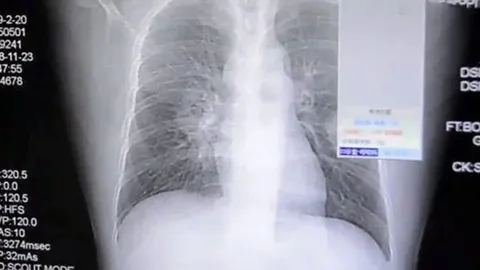

ติดสูดดมถุงเท้าจนปอดพัง